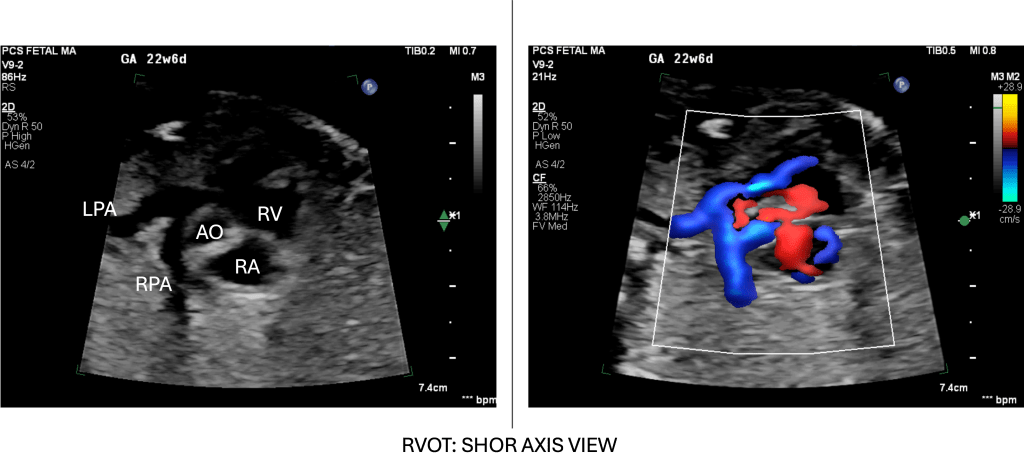

- Short-Axis (RVOT Outflow) Sweep

- From the 4-chamber view, rotate/sweep cranially and slightly cranial-right to bring the right ventricular outflow tract (RVOT) into view.

- In this short-axis cut, the main pulmonary artery arises anteriorly from the RV, and by sweeping slightly, its division into branch PAs (leftward and rightward) is displayed.

- If we continue this view posteriorly, this will continue as a ductal arch. Alternatively, we can trace the branch PAs anteriorly from the ductal arch